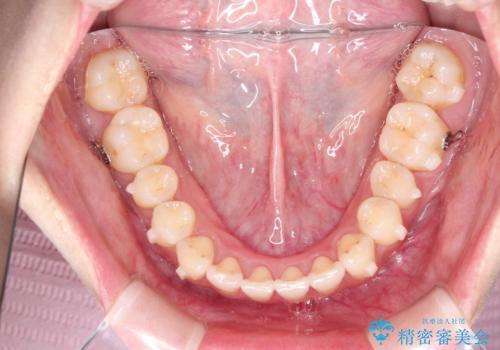

見た目、嚙み合わせ及び、治療期間や施術内容に大変ご満足いただきました。